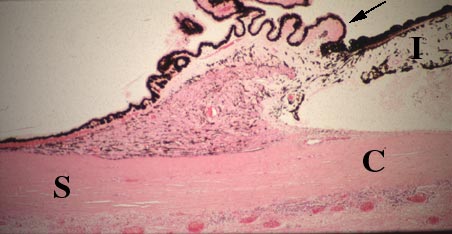

IX-28C Sclera (S), cornea (C), iris (I) and ciliary processes (arrow) are seen.